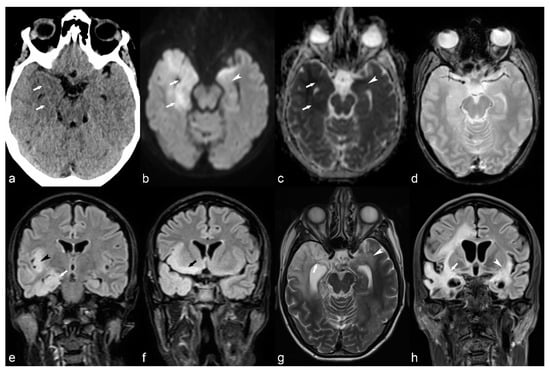

Figure 7.

(a) 25-year-old female with Tuberosis Sclerosis Complex (TSC). Axial CT image (a) shows multiple calcified subependymal nodules (arrows). (b–e) Another 23-year-old female with TSC. Axial T1 weighted image (b) showing multiple subependymal hyperintense nodules (arrows). Coronal FLAIR (c) with curvilinear multiplanar reformat (d) shows multiple cortical tubers with radiating subcortical white matter hyperintensity (arrowheads). PET CT (e) shows hypometabolic areas corresponding to cortical tubers in bilateral occipito-temporal and left temporal region (arrows). (f) 14-year-old male with TSC. Coronal reformat of 3D T1 post contrast image (black arrowhead) shows enhancing subependymal giant cell astrocytoma abutting the floor of frontal horn of left lateral ventricle.